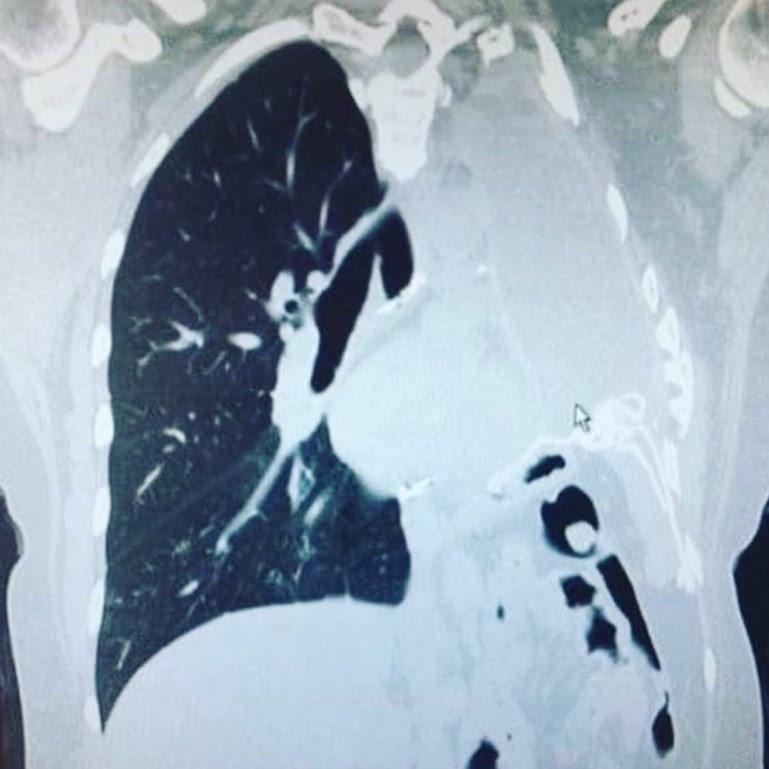

Yapılan tomografi sonucu akciğerine yakın bir bölgede tümör tespit edildi ve plevral mezotelyoma teşhisi kondu.

2006 yılında yapılan ameliyatta sol akciğeri, bir kaburgası, akciğer zarı (plevra), diyaframının bir kısmı ve kalp zarı alındı. Ameliyat sonrası ise bayana 4 kür kemoterapi ve 30 seans radyoterapi uygulandı.